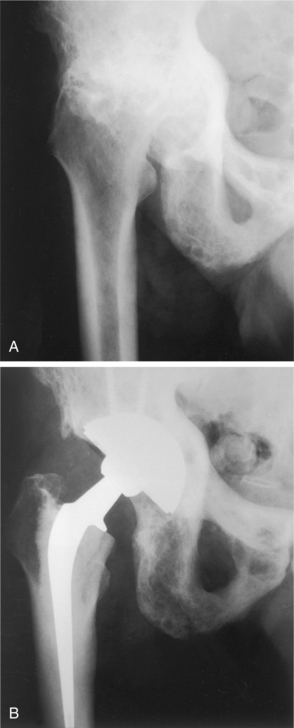

Fractures are usually diagnosed by radiograph examination (x-ray) that demonstrates the fracture (Fig. 24-5) and also reveals the osteopenia leading to the diagnosis of osteoporosis. Once osteopenia is noted, other causes of metabolic bone disease must be ruled out, including hyperthyroidism, hyperparathyroidism, osteomalacia, testicular failure, malignancies, and so on. Diagnostic criteria for men with this condition are at present based on those for women, although the validity of this approach is under discussion.131 Histologically, a thinning of cortical bone and a reduction in the number and size of the trabeculae of cancellous bone occurs (see Fig. 24-1). Thirty percent or greater bone density loss must occur before such abnormalities can be noted on an x-ray film.

Figure 24-6 Osteomalacia of the femur. Note the loss of the sharp interface between cortical bone and cancellous bone caused by demineralization of the cortex. (From Richardson JK, Iglarsh ZA: Clinical orthopaedic physical therapy, Philadelphia, 1994, WB Saunders.)

Figure 24-7 Osteomalacia. A, Forearm and B, femoral neck. Looser zones are seen as translucent zones with sclerotic margins. Usual sites include the medial femoral neck, pubic rami, lateral borders of the scapulae, and ribs. Complete fractures can extend through Looser’s zones; these will heal with appropriate treatment. (From Bullough P: Orthopaedic pathology, ed 3, London, 1997, Mosby-Wolfe.)